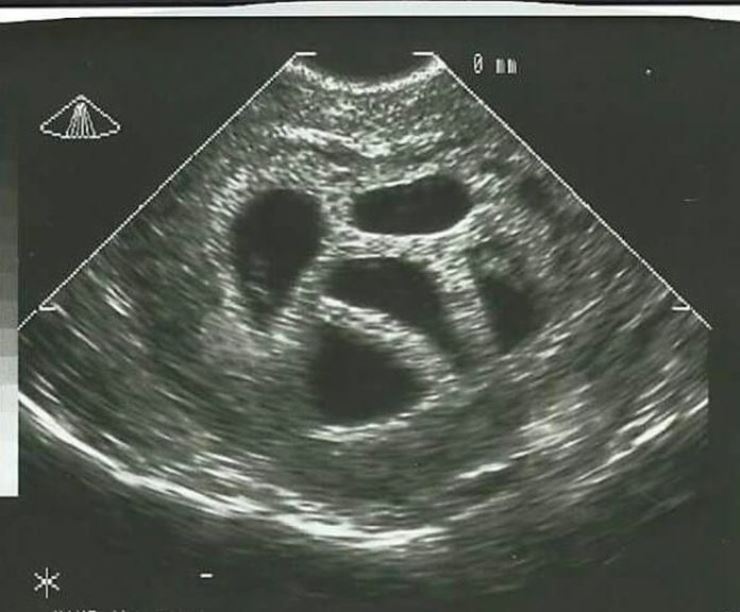

“U dobi od 28 godina saznala sam da sam trudna i to s petorkama. Moj liječnik odmah mi savjetovao selektivni pobačaj, prenosi Narod hr.